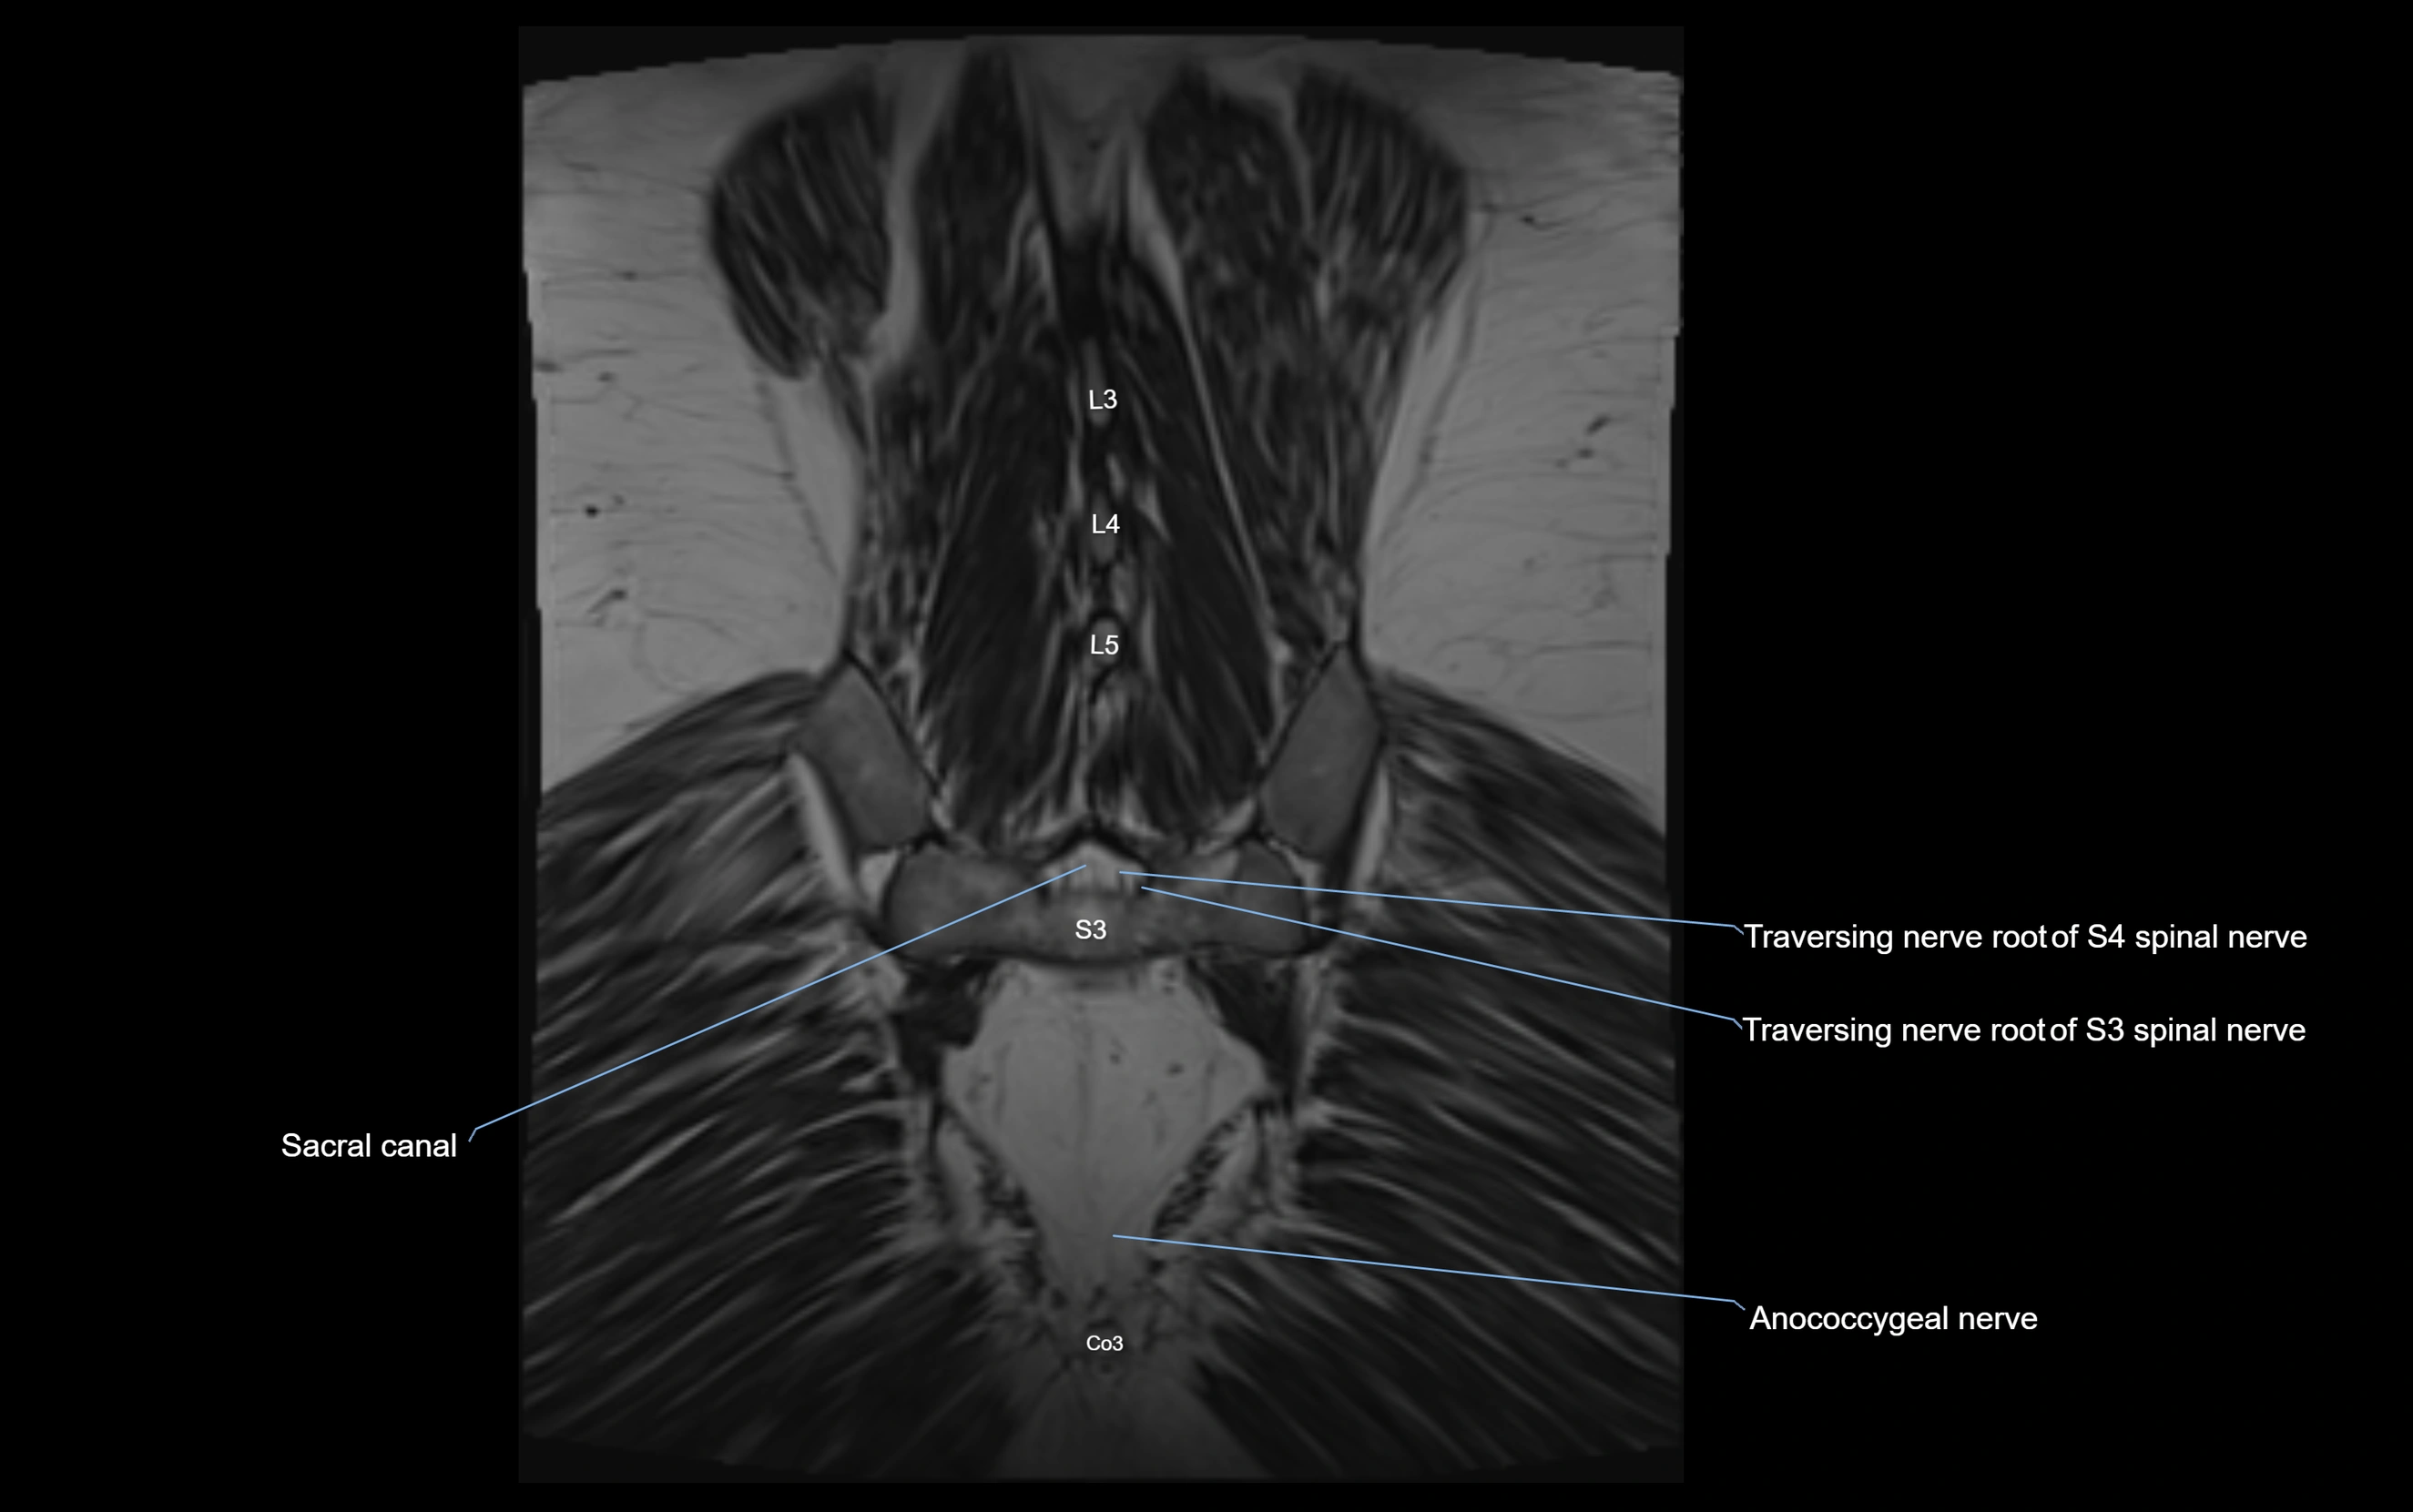

Anococcygeal nerve

The anococcygeal nerve is a small sensory nerve derived from the coccygeal plexus, which itself is formed by the ventral rami of S4, S5, and the coccygeal nerve (Co1). Although tiny, this nerve plays an important role in supplying the skin of the coccyx and the area between the anus and coccyx. It passes through the sacrotuberous ligament and runs in the midline behind the coccyx.

Despite its small size, the anococcygeal nerve is clinically important because of its involvement in coccygodynia (coccyx pain) and perineal pain syndromes.

Origin, Course, and Branches

• Origin:

• Arises from the coccygeal plexus, formed by ventral rami of S4, S5, and Co1

• Course:

• Emerges through the sacrotuberous ligament near the coccyx

• Runs in the midline posterior to the coccyx

• Passes forward into the small space between anus and coccyx

• Branches:

• Small cutaneous branches that supply the skin between the coccyx and anus

MRI Appearance

3D T2 SPACE / CISS:

• Nerve appears intermediate to mildly hyperintense compared to muscle

• Surrounded by bright fat or CSF, improving visualization

• Best sequence for mapping small pelvic nerves such as the anococcygeal

MRI image

image